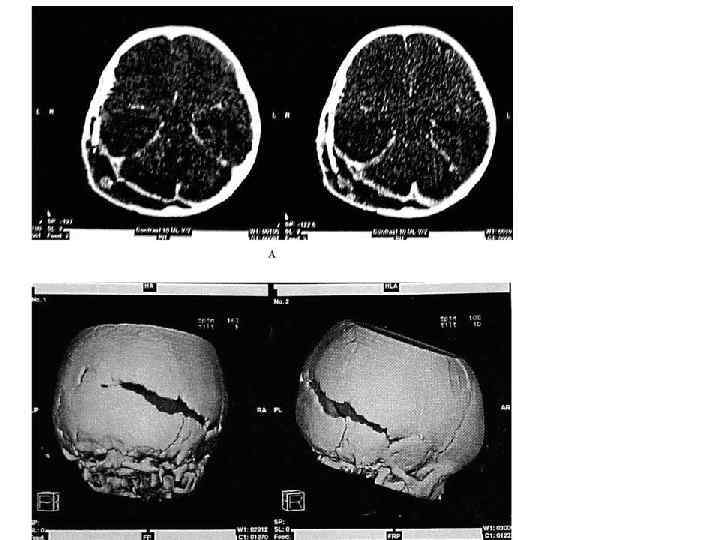

Вид перелома